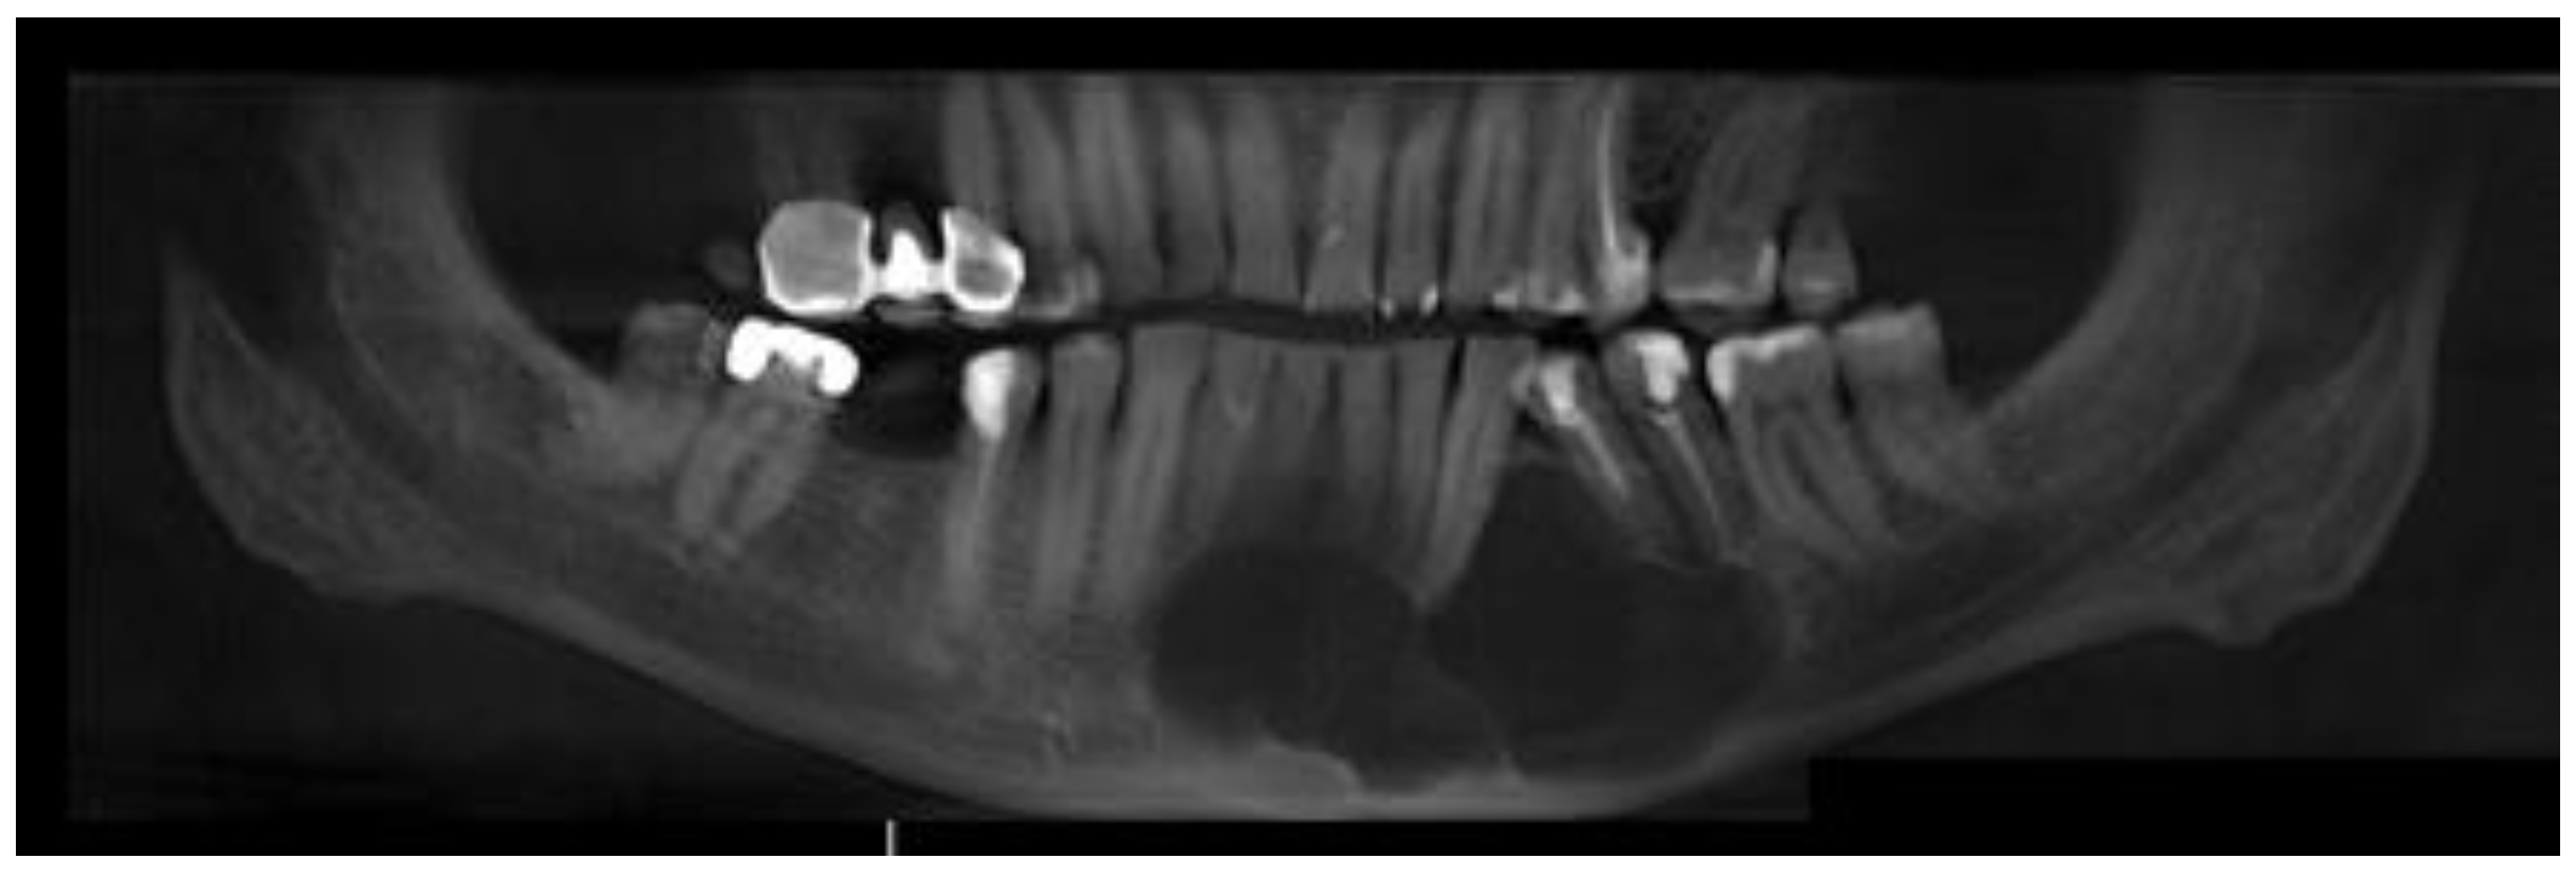

A 62-year-old Caucasian male was referred for consultation because of a cyst in the mandibular anterior and left body area associated with teeth mobility. The lesion was incidentally discovered by a dentist on a routine panoramic radiograph. On imaging, there was a polycystic lesion, quite big in diameter, with well-defined borders, visible inner cystic septa, and displaced 33,34,35 teeth. The cystic cavity ranged from tooth 43 towards 36, causing superior destruction of the alveolar ridge between teeth 33 and 34 and inferiorly spreading closely towards the inferior margin of the mandible. This expansive lesion was radiolucent with some septa with cortical buccal and alveolar ridge expansions (Figure 1).

Figure 1. A panoramic radiograph reconstruction based on CBCT imaging with visualized cystic cavity.